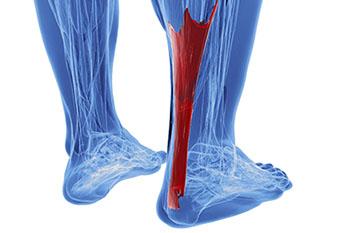

Achilles Tendon

The Achilles tendon is not only the strongest, but also the largest tendon in the human body. The main function of the Achilles tendon is to transmit power from the calf muscles to the heel and the foot. It’s because of the Achilles tendon that we are able to stand on...